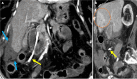

Endoscopic retrograde cholangiopancreatography (ERCP) is a cornerstone procedure for the diagnosis and management of pancreatic and hepatobiliary diseases. Although its diagnostic role has been increasingly supplanted by noninvasive imaging modalities such as magnetic resonance imaging (MRI) and magnetic resonance cholangiopancreatography, the therapeutic applications of ERCP have continued to expand. ERCP is widely used and has a generally favorable safety profile. However, it is important to recognize expected post-procedural imaging findings and serious complications that can arise. The increasing complexity of therapeutic interventions and the growing volume of procedures have led to a higher incidence of complications that often present with overlapping clinical and laboratory features, underscoring the critical role of imaging in differential diagnosis. This review focused on the typical normal ERCP findings and the imaging characteristics of common complications, including pancreatitis, bleeding, ERCP-related infections, perforations, and stent-related complications. Computed tomography (CT) is particularly valuable in timely recognition, management, and surgical decision-making for these complications. Furthermore, MRI offers a radiation-free alternative for managing complications in selected patients. Therefore, radiological modalities, particularly CT and MRI, are critical tools for the rapid diagnosis, management, and surgical decision-making processes for post-ERCP complications.